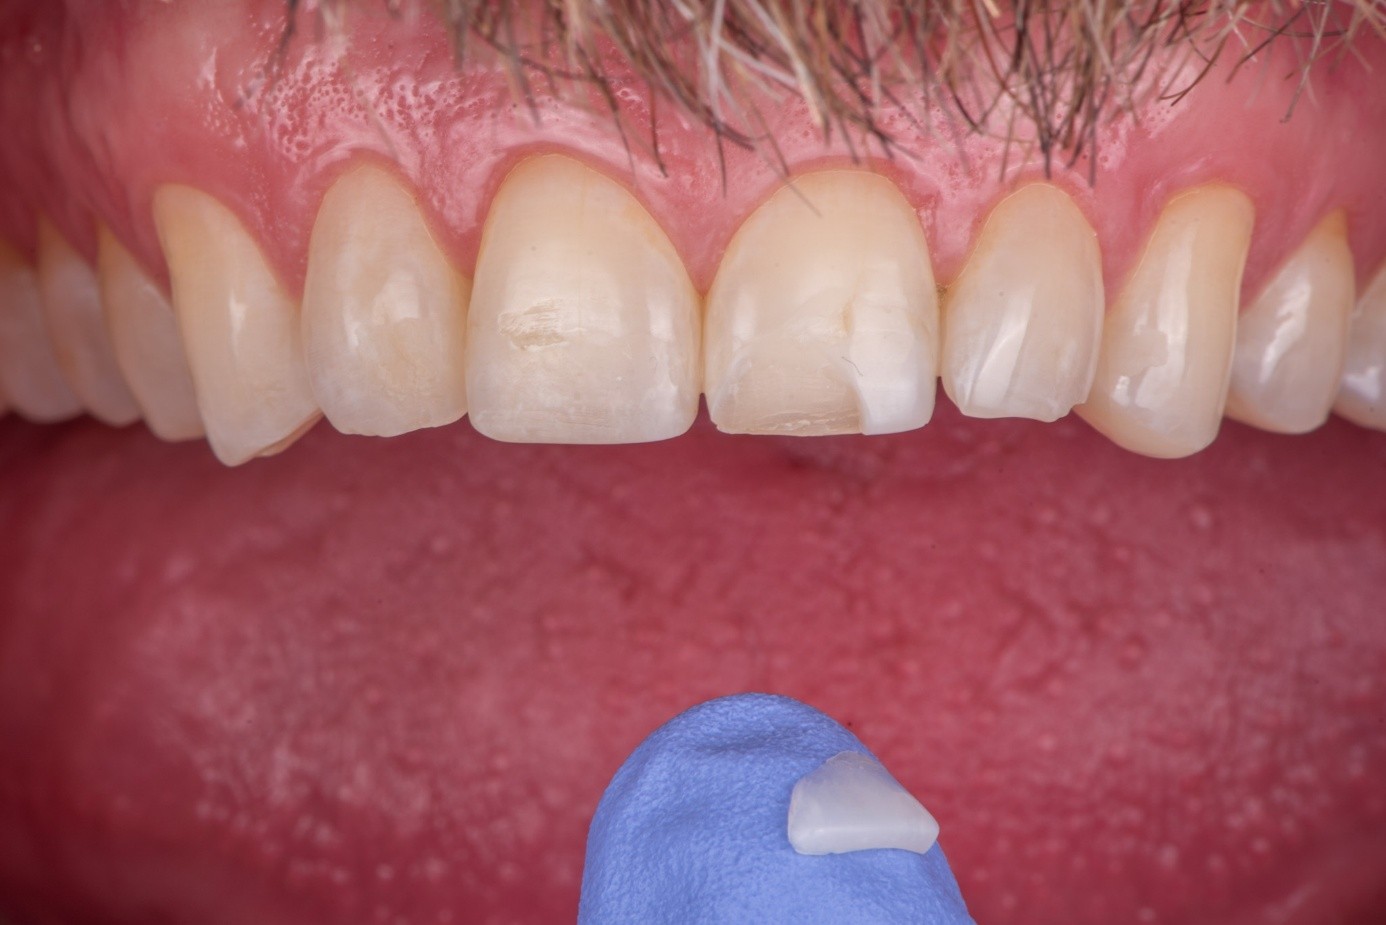

Case 1: Broken Feldspathic Veneer

This case involved a patient with multiple feldspathic porcelain restorations done more than 15 years ago in the esthetic zone. Multiple restorations presented with tissue recession and marginal discoloration, some also presented with microcracks that were visible during clinical examination and were in need of replacement in the near future. However, the patient was not financially committed to replace the other failing restorations. Maxillary right lateral incisor presented with an unusual failure pattern: The incisal third remained fully bonded and intact, while the middle-to-cervical portion of the veneer was fractured away as a single piece (Figure 2). This type of fracture could be described as a cervical shear fracture with incisal retention—a form of mixed failure, since part of the restoration remained bonded but the majority separated cleanly. Examination revealed almost no adhesive layer on the tooth surface, while the fractured restoration still showed adhesive remnants (Figure 3). This indicated that the weak point was the interface between adhesive and tooth substrate, rather than between ceramic and adhesive.

(2.) An intraoral view of the maxillary anterior region, where most teeth are restored with ceramic facings. The upper lateral incisor is fractured, with only the ceramic in the incisal third remaining in place. The cervical and middle thirds of the facing are lost, exposing the underlying tooth structure.

Figure 2